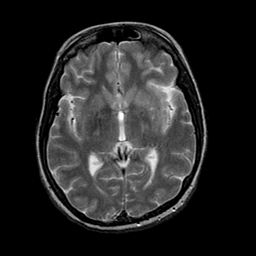

Acute Stroke: T2-weighted MR -- Slice #13

[Home][Help][Clinical][Tour 1] Slice 13